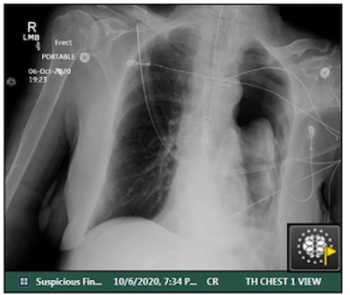

Adjunctive use of the AI-powered software led to an average 38.6 percent increase in the detection of pneumothorax by general radiologists, according to a 2023 study.

For clinically actionable pneumothorax, an artificial intelligence algorithm demonstrated a 93 percent AUC and a 96 percent specificity rate in a study involving chest X-rays from over 27,000 adults.